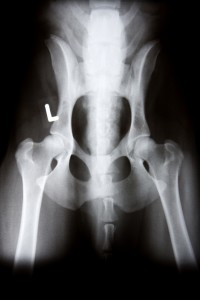

Critter Fixer Veterinary Hospital is proud and excited to offer the latest in x-ray technology – digital radiology. Until recently, x-ray technology had remained basically unchanged for almost a hundred years. New digital x-ray systems have vastly improved our diagnostic abilities by using computers to aid in the capture and manipulation of the image (including magnification) to see certain conditions more clearly. It also means you can view your pet’s x-rays on the computer screen in the exam room and we can e-mail x-rays to specialists for review. The results are excellent! In addition, we no longer have to use the chemicals associated with processing x-ray film – a plus for the environment and our staff! Now x-rays are safer, quicker, and much more useful. They can be stored in a digital format and sent over the web for consultation with a specialist if necessary. Critter Fixer Veterinary Hospital has invested in this revolutionary technology to better serve you and your four legged companions.